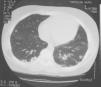

Caso 1: niña de 12 años, con antecedente de traumatismo de tobillo izquierdo 3 días previo al ingreso hospitalario, que presentó fiebre, vómitos, dolor intenso en el miembro inferior derecho, dolor restroesternal y disnea. Se diagnosticó por RM de osteomielitis tibial izquierda con discreto absceso subperióstico e importante afectación de la musculatura adyacente. La TC torácica mostró múltiples imágenes nodulares y pequeñas cavitaciones en ambos campos pulmonares compatibles con émbolos sépticos (fig. 1). En hemocultivo se identificó SAMS productor de LPV. La identificación microbiológica se realizó por métodos convencionales, la sensibilidad antimicrobiana se determinó mediante el sistema Vitek 2, usando la tarjeta AST-P549 (bioMérieux) y la detección de los genes codificantes de LPV (lukS-PV y lukF-PV) se realizó mediante reacción en cadena de la polimerasa convencional en el CNM. La paciente recibió tratamiento antibiótico durante 35 días (cloxacilina más clindamicina 19 días, seguido de cefadroxilo por vía oral 16 días) y anticoagulación durante 6 semanas. A los 3 meses se evidenciaron imágenes compatibles con osteomielitis crónica, por lo que recibió 12 semanas adicionales de cefadroxilo y se realizó limpieza quirúrgica, con buena evolución posterior.